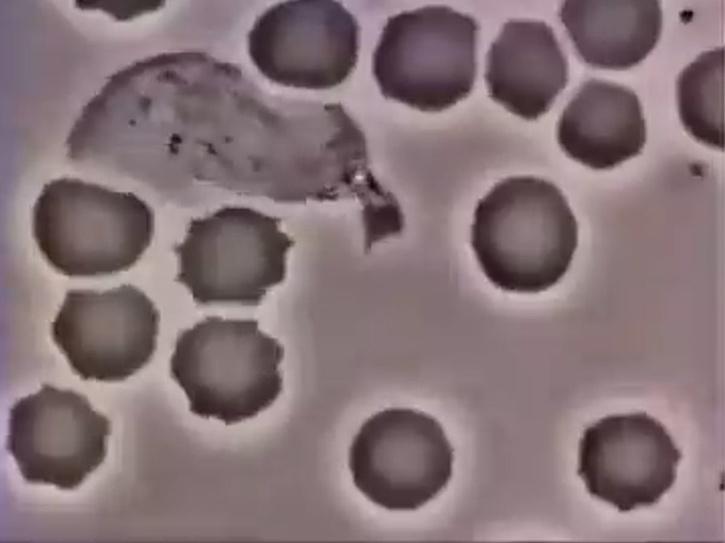

El estudio muestra cómo las membranas celulares se doblan para crear «bocas» que ayudan a las células a consumir cosas a su alrededor. «Al igual que nuestros hábitos dietéticos que forman la base de cualquier cosa en nuestro cuerpo, la forma en que ‘comes’ las células es importante para la salud celular», dijo a Phys Kumart Corral, profesor asistente de física en la Universidad Estatal de Ohio y autor principal del estudio. org. .

Coral agregó que los científicos solo entienden su mecánica ahora. El estudio fue publicado en la revista Development Cell el mes pasado y encontró que «la maquinaria intercelular de la célula se ensambla en una estructura similar a una canasta altamente curvada que eventualmente crece hasta convertirse en una jaula cerrada».

El estudio destaca los senos que recogen el material que se acerca a la célula antes de que se convierta en vesículas, pequeños sacos que tienen una décima parte del tamaño de un glóbulo rojo.